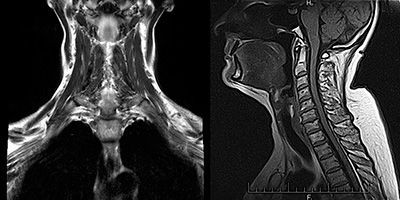

МРТ мягких тканей шеи

МРТ мягких тканей является неинвазивной инструментальной методикой диагностических исследований, позволяющей получить высокоинформативные изображения исследуемой области. Она позволяет осуществлять диагностику целого ряда патологий и аномалий развития, а также травм и повреждений. В случае, если необходимо добиться максимально чёткого изображения, проводят МРТ мягких тканей с контрастом.